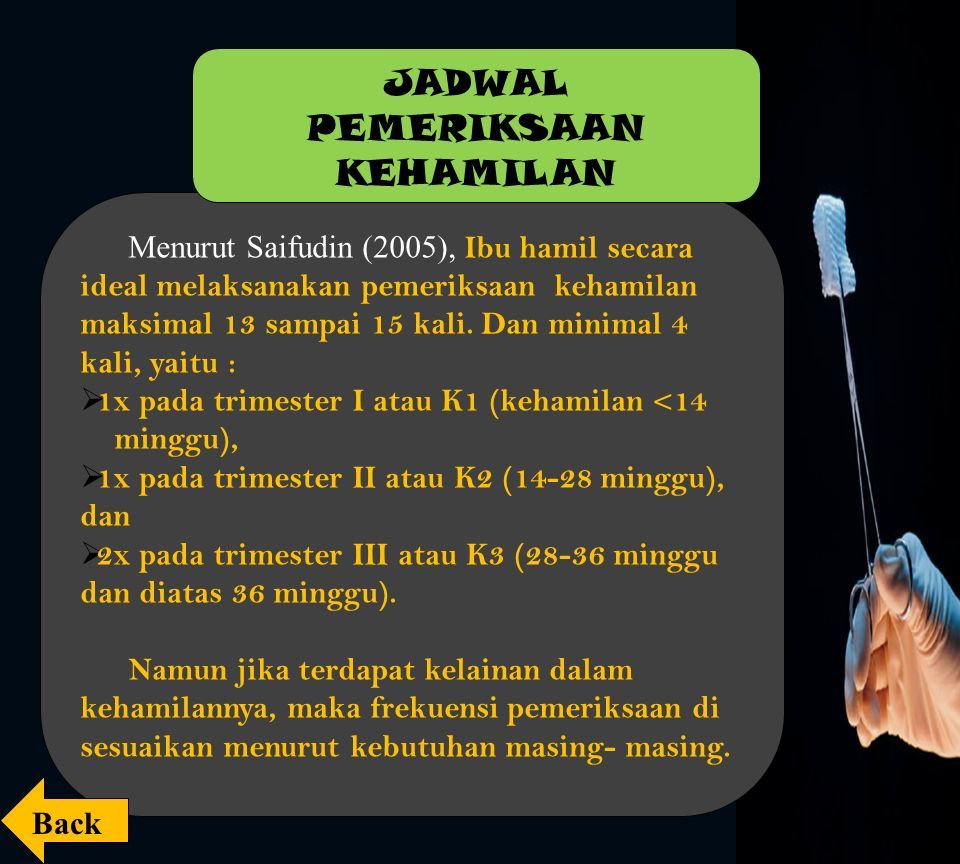

Asuhan Pada Kehamilan Trimestar 3 Tujuan Pemeriksaan Jadwal Pemeriksaan Kehamilan Usia Kehamilan Pengertian Dampak Tidak Memeriksakan Kehamilan Daftar Ppt Download

Asuhan Pada Kehamilan Trimestar 3 Tujuan Pemeriksaan Jadwal Pemeriksaan Kehamilan Usia Kehamilan Pengertian Dampak Tidak Memeriksakan Kehamilan Daftar Ppt Download